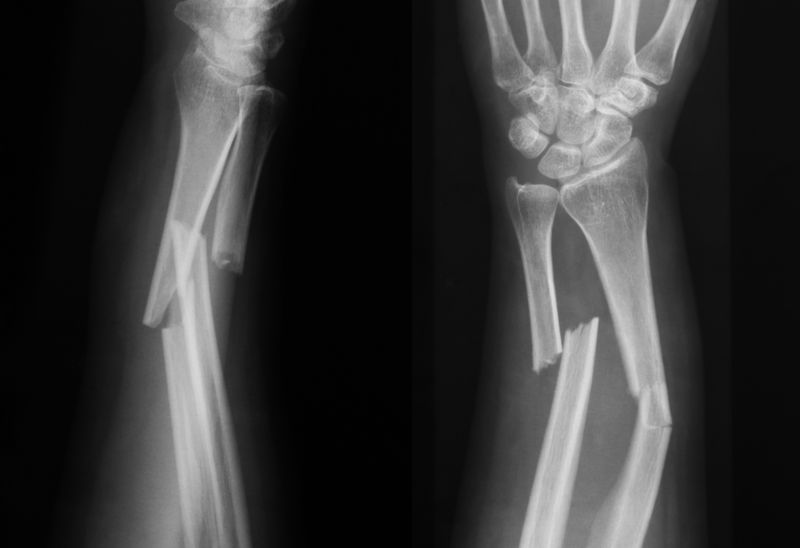

Broken Bones

A fracture is a break in the bone. The only way to diagnose a fracture is by obtaining an Xray. Lani City Medical Urgent Care offers Xray on site. If you have suffered an injury and want to make sure you do not have a fracture, walk into Lani City Medical Urgent Care and get answers fast.